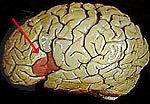

與語言相關的大腦部位語言時通過套用符號達到交流的能力,包括對符號的運用和接受的能力。符號包括口頭和書面的符號(文字),還應包括姿勢語言(手語或啞語、手勢)。

1861年Broca發現一病例,喪失言語和書寫能力,但理解口語。屍解證明病變累及左大腦半球額中、下回。

1874年Wernicke發表著名的“失語症狀學”描述了左顳上回為聽中樞控制聲的印象,稱此為感覺性失語。額下回後部控制聲的運動印象,成為後來的運動性失語。Wernicke認為此二區必有聯繫,此聯繫中斷必產生第三種失語。1885年Lichteim從臨床證明第三種失語——傳導性失語。

Broca失語病灶部位相當於Brodmann44區。

病灶部位在優勢半球顳上回後部,辭去通常稱為聯合皮質。實際病灶大多明顯大於顳上回後部的Wernicke區。

病灶位於左側Broca區和Wernicke區之間的聯繫纖維(弓狀纖維),相當於左顳頂區,主要在緣上回。